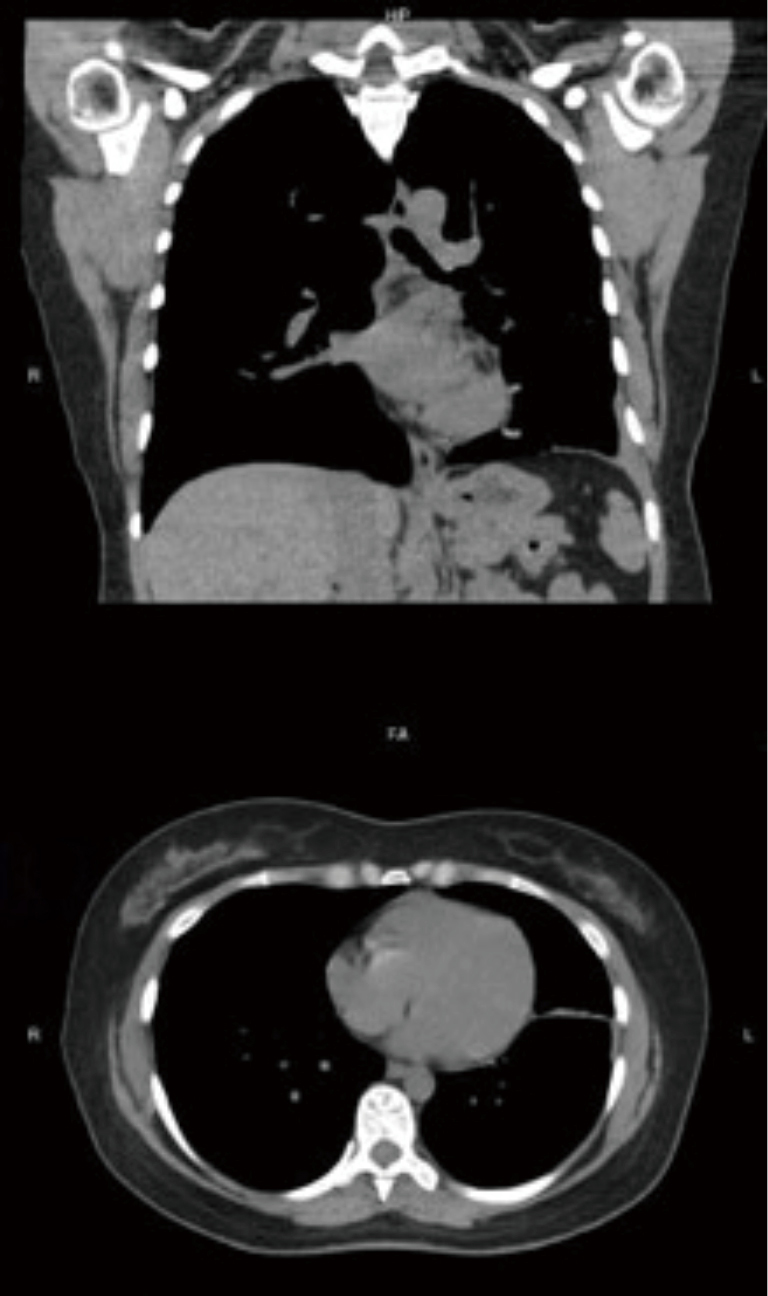

Tracheobronchial stenosis in a 45yearold man. Contrastenhanced CT Tracheobronchial Stenosis subglottic stenosis and tracheal stenosis (ts) are broad terms that describe a stricture or narrowing of the. tracheobronchial stenosis results from malignant and benign causes. Treatment includes systemic therapy in addition to. tracheobronchial stenosis, narrowing of the airways by neoplastic or nonneoplastic processes, may be focal, as occurs with. significant tracheal stenosis typically requires management by.. Tracheobronchial Stenosis.